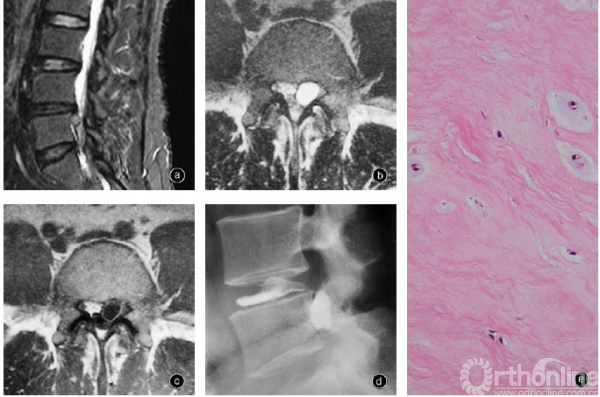

图4 椎间盘囊肿 a 男,51岁,左下肢放射痛,矢状面MRI抑脂像示L4-5椎间盘囊肿。后路脊柱内镜术中见囊肿与椎间盘相连,囊内有液体和髓核碎片 b 男,27岁,L4-5椎间盘囊肿,横断面MRI T2WI示L5椎体后侧边界清晰的高信号卵圆形囊肿影 c 在Gd DTPA强化的MRI T1WI上囊肿壁明显强化 d 椎间盘造影示囊肿被造影剂充填,囊肿与椎间盘下角相连 e 男,29岁,L5S1椎间盘囊肿的囊肿壁内含软骨组织和椎间盘的纤维基质 HE染色×400

椎间盘囊肿临床上较罕见,既往文献中的确诊病例约为100例,男性多于女性,平均发病年龄约33岁。Chiba等报告8例,并总结其特征为发病年龄较椎间盘突出相对小,临床表现与典型的椎间盘突出症相似,常为单侧神经根受累;MRI表现为T1加权像低信号、T2加权像高信号的圆形或椭圆形含液体的囊肿团块,受累的椎间盘退变轻微;椎间盘造影示囊肿与受累的椎间盘相通,注射时可引起下肢严重放射痛;手术切除囊肿后临床症状明显缓解;病理检查囊肿壁有致密纤维结缔组织,内容为从血性到完全清亮的血清,无椎间盘组织和特殊内衬细胞层(图4)。

椎间盘囊肿是与椎间盘相通的囊肿,很少见,需要与其他椎管内囊肿进行鉴别,如起源于关节突关节的邻关节滑膜囊肿、神经周围囊肿、神经节囊肿、蛛网膜囊肿、后纵韧带囊肿等。椎间盘囊肿与后纵韧带囊肿都位于硬膜囊腹侧,与椎间盘或后纵韧带通过蒂紧密连接,内壁均为纤维结缔组织,无滑膜内衬,临床表现和治疗类似。但椎间盘造影或手术时可见囊肿与椎间盘相通,切除囊肿后可出现椎间盘纤维环缺损。

(一)病理学改变和发病机制

组织学检查可见椎间盘囊肿壁为致密纤维结缔组织,有含铁血黄素沉着和黏液变性,无细胞内衬,无椎间盘组织、神经组织和肿瘤细胞,无新的血管化和细胞浸润。囊内为血性或血清样清亮的液体,囊壁与椎间盘连接,有时可发现与椎间盘连通的管道,纤维环有小撕裂。手术切除时一般粘连很轻微。但也有研究证实椎间盘囊肿的囊壁含有软骨等椎间盘组织。

椎间盘囊肿的原因和发病机制尚不明确。Chiba等认为椎间盘囊肿含有血性液体和含铁血黄素沉着,可能源于椎间盘损伤和纤维环后侧撕裂、椎体后壁的硬膜外静脉丛出血形成血肿,损伤和出血反应形成纤维结缔组织囊壁包裹,类似于半月板囊肿。Kobayashi等认为椎间盘局部退变和损伤使椎间盘突出和椎间盘内液体溢出,并引起炎性反应和反应性假膜形成囊肿;患者年纪轻,椎间盘含水多,液体渗入囊肿形成囊液;囊肿可造成骨侵蚀说明压力高,可能存在止回阀机制,压力和体积可在短时间内增大,需严密观察。Toku⁃naga等报告2例MRI显示的椎间盘突出转变为椎间盘囊肿,并在囊壁发现软骨组织,推测椎间盘突出吸收时形成纤维组织包膜和新生血管长入,单核巨噬细胞吞噬突出髓核,囊壁内出血积聚,直至囊内压力增高、血肿吸收。